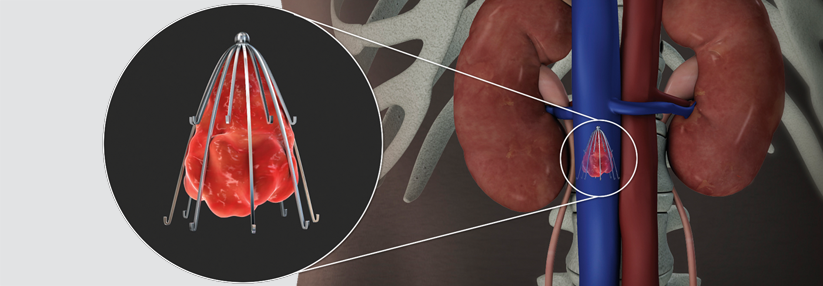

Bei schwerer akuter Lungenembolie (LE) in der Notaufnahme sollten Risikostratifizierung und Therapievorschlag individualisiert durch ein multidisziplinäres LE-Team erfolgen, erklärte Dr. Kai-Helge Schmidt von der Universitätsklinik für Kardiologie in Mainz. Besteht ein eher geringes Blutungsrisiko, ist die intravenöse Thrombolyse Standard, bei hohem Risiko eher ein kathetergestütztes interventionelles Verfahren. Allerdings gibt es keinen etablierten Score für die Abschätzung des Blutungsrisikos in dieser Situation, erläuterte Dr. Schmidt.

Bei Hochrisiko-LE ist die Evidenz für die Thrombolyse besser als für die Embolektomie. Letztere wird vorzugsweise dann empfohlen, wenn eine medikamentöse…